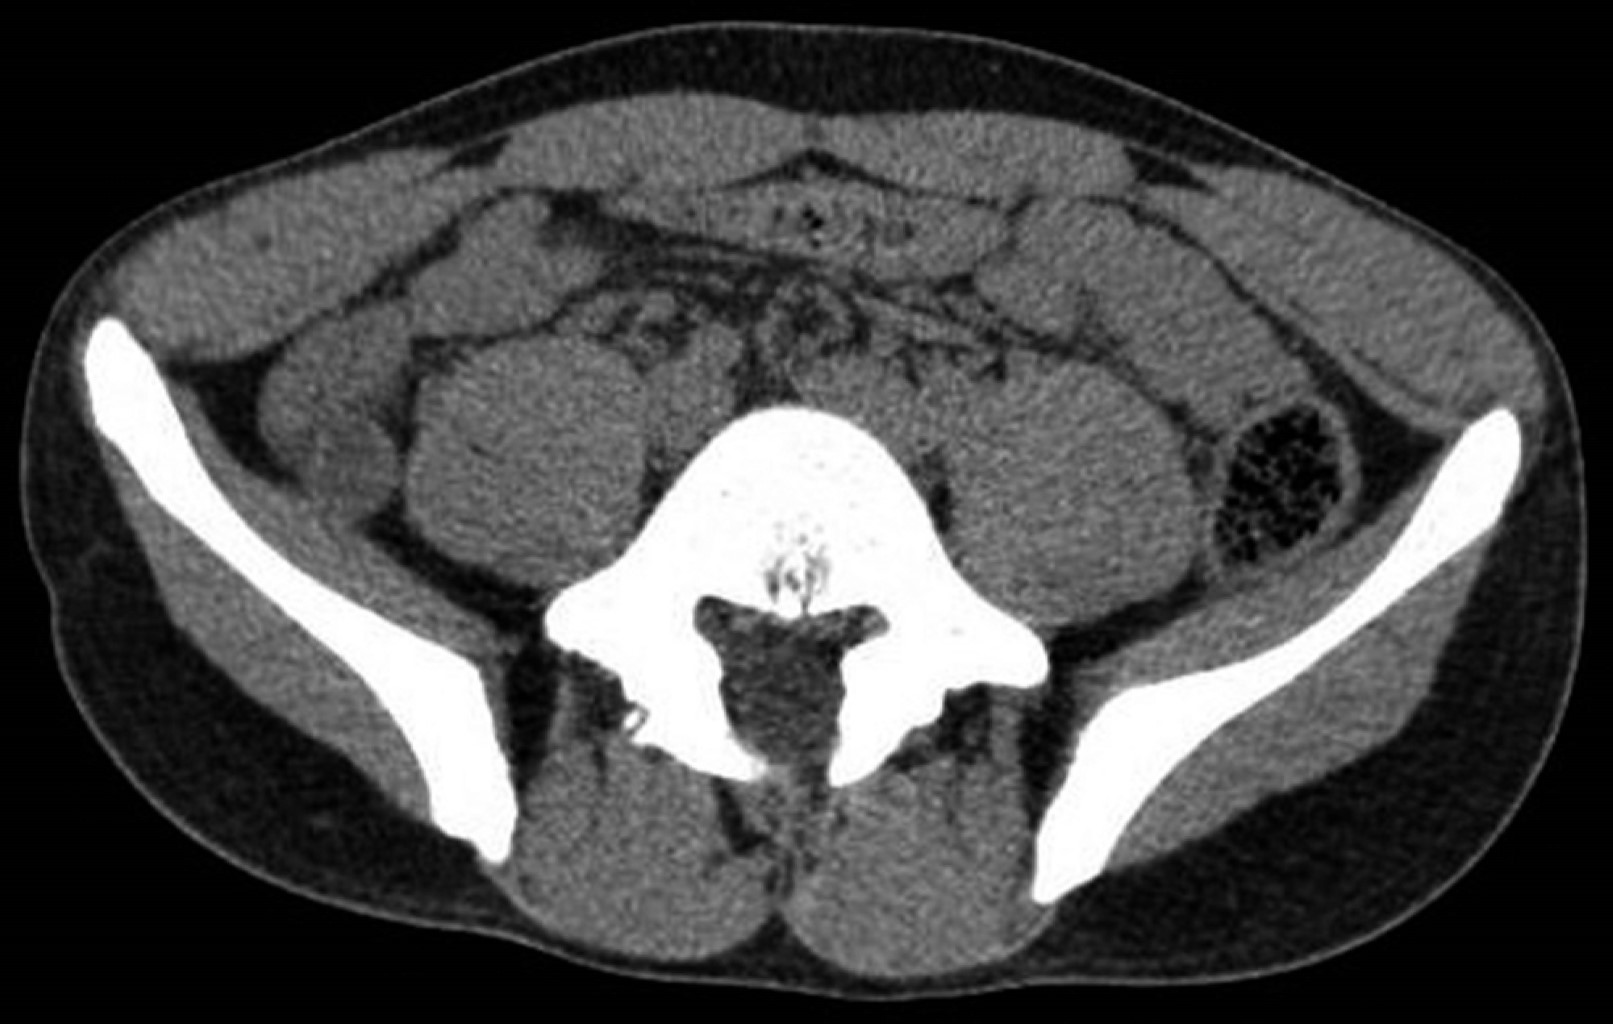

Hombre de 19 años que niega antecedentes quirúrgicos, así como crónicos degenerativos. Al interrogatorio de antecedentes familiares de cáncer, todos fueron negados. Se presentó al servicio de urgencias con dolor abdominal de tipo cólico, de inicio periumbilical irradiado a fosa ilíaca derecha, acompañado de náuseas, vómito de contenido gastroalimentario en tres ocasiones e intolerancia a la vía oral, a la exploración física contó con datos de irritación peritoneal. Se realizaron estudios de laboratorio con leucocitos de 10.97 × 109/L y neutrófilos de 85%. Se realizó tomografía de abdomen donde se reportó ileítis terminal con ganglios mesentéricos de aspecto reactivo, apéndice cecal con diámetro limítrofe de 6 mm sin visualizar la punta (Figura 1). Al presentar cuadro de abdomen agudo con alta sospecha de apendicitis aguda se efectuó laparoscopía diagnóstica y apendicectomía (Figura 2); los hallazgos de importancia de dicho procedimiento fueron: apendicitis aguda, abscedada, con un absceso de hueco pélvico de 15 cm3, se decidió manejo del muñón apendicular con ligadura simple e invaginación con punto en Z, reportando un sangrado de 10 cm3. Se envió a patología pieza quirúrgica y dos semanas después se entregó reporte con diagnóstico de tumor neuroendócrino bien diferenciado grado 1, según clasificación de la OMS (Figura 3), con las características comentadas en la Tabla 1.

Figura 1